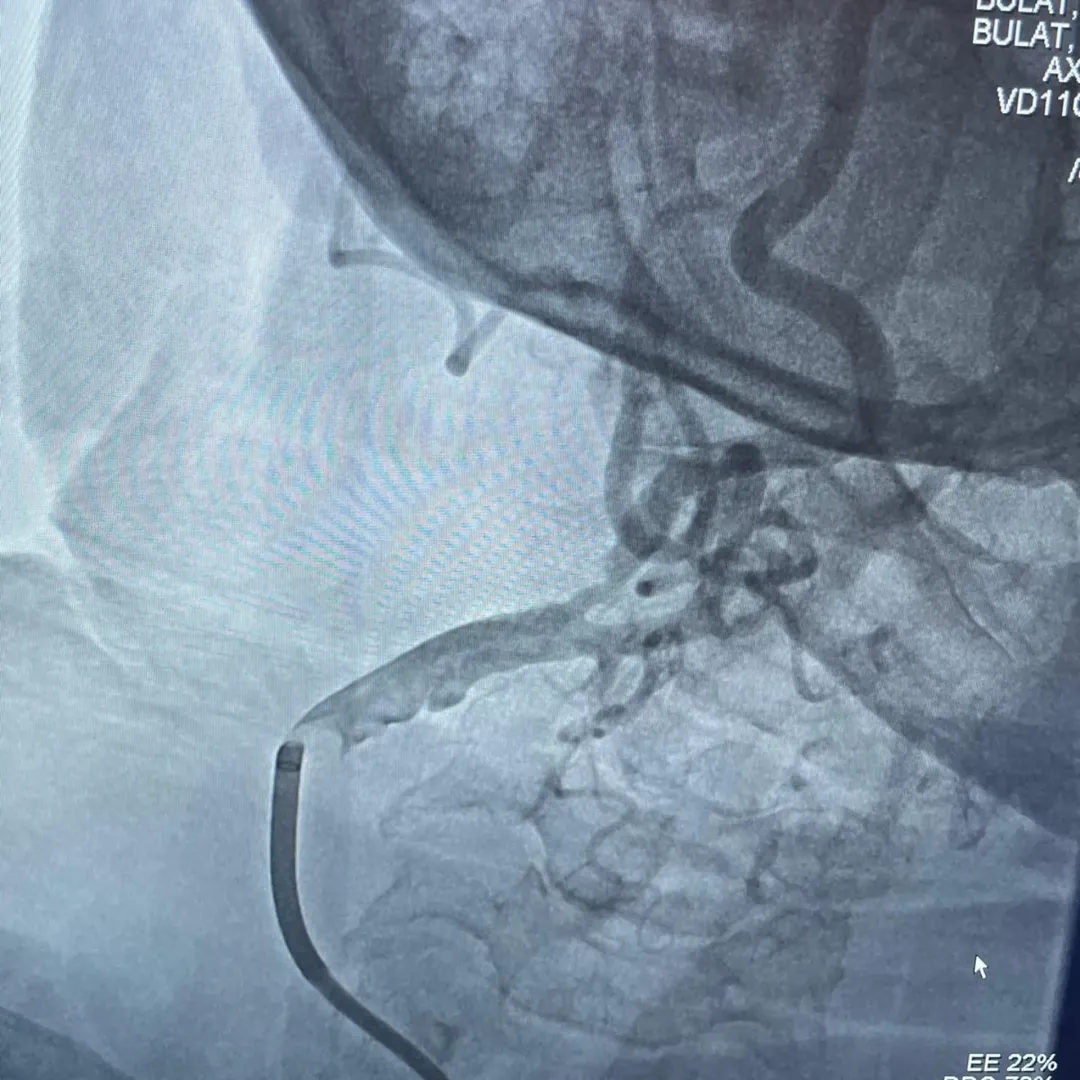

Workshop kapsamında karotis arter stentleme, subklavyen arter stentleme ile kalsifik koroner lezyonlarda Rotablator, IVL ve OPN NC balon teknikleri ele alındı. Katılımcılara teorik bilgilerin yanı sıra modern cihazlar kullanılarak uygulamalı eğitim verildi.

Eğitimde, kompleks damar lezyonlarının tedavisinde kullanılan güncel yöntemler, işlem planlaması ve yeni teknolojilerin klinik kullanımı hakkında bilgi paylaşıldı. Yetkililer, sağlık çalışanlarının mesleki gelişimini destekleyen bilimsel etkinliklere önem verdiklerini belirterek, nitelikli sağlık hizmeti sunmaya yönelik çalışmaların süreceğini bildirdi.